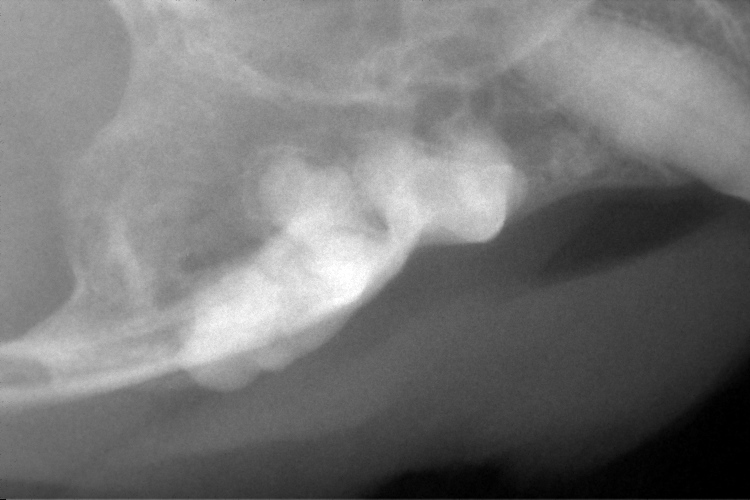

歯科レントゲン

右上顎第3前臼歯です。

遠心根が溶けて無くなっていることが確認できます。